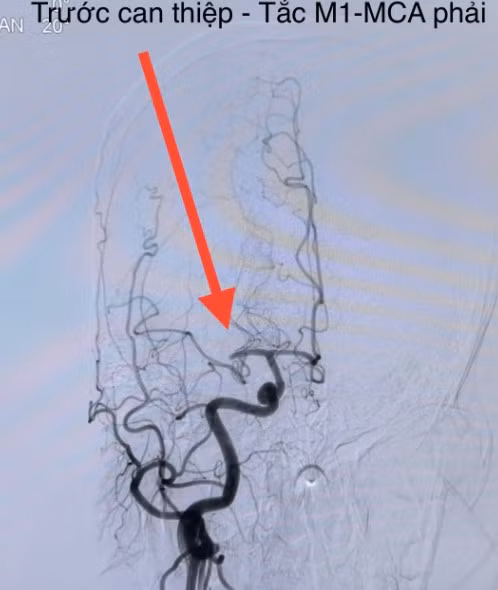

![]() |

| Hình ảnh đột quỵ não do tắc nghẽn mạch máu não - Ảnh BSCC |

Các thủ thuật can thiệp nội mạch: bác sĩ có thể tiến hành lấy huyết khối trực tiếp bằng ống thông hút huyết khối, stent kéo huyết khối trên máy chụp mạch số hoá xoá nền (DSA). Thời gian càng sớm càng tốt, đối với các người bệnh nhồi máu não cấp do tắc động mạch lớn và có thể điều trị trong vòng 24 giờ kể từ thời điểm người bệnh còn bình thường. Từ đó các cục huyết khối sẽ được lấy ra và tái thông mạch máu não cho người bệnh.